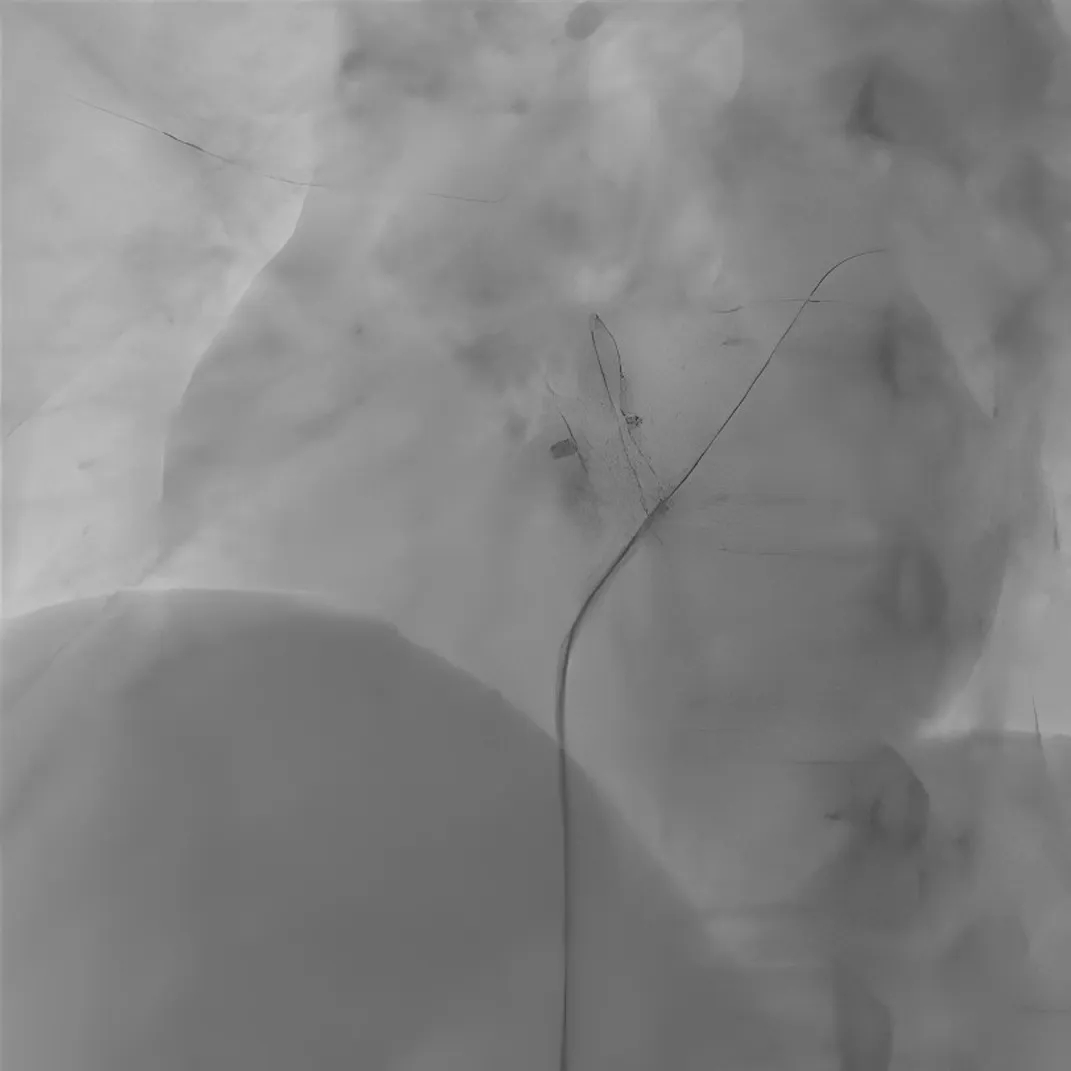

图3 导丝及导管经残余分流处进入左心房

患者随后接受了针对卵圆孔未闭残余分流的二次封堵手术。右心导管检查测得肺动脉压力为27/10mmHg(平均压20mmHg),肺动脉造影排除了肺动静脉瘘。使用6F MPA2导管(Cordis)进行选择性房间隔造影,显示原植入的封堵器下缘存在显著右向左分流(图2)。导丝及导管成功通过残余分流处进入左心房(图3),随后将6F MPA2导管送至左上肺静脉。交换260cm加硬导丝至肺静脉,随后将12F输送鞘管沿导丝输送至左心房。成功释放一枚18/18mm对称型Memosorb可降解卵圆孔未闭封堵器(乐普医疗),有效封闭了残余分流(图4)。封堵器释放成功后立即进行选择性房间隔造影,未见明显残余分流。经胸超声心动图及透视检查均确认封堵器位置良好、形态完整(图5)。术后即刻行经胸超声心动图联合右心声学造影复查,亦未见明显残余分流(图6)。